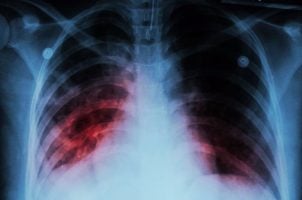

TB is a life-threatening bacterial infection that usually attacks the lungs. Treatment for active TB involves prolonged antibiotics courses of between four and 20 weeks. That’s because some strains of the disease are resistant to certain medications.

Around 90% who get the disease are asymptomatic and cannot pass it on, known as latent TB. For the 10% who develop active TB, like V.N., the death rate is around 66% if effective treatment is not received.